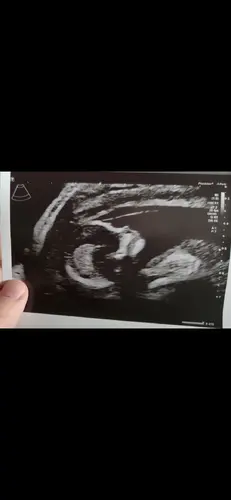

Wat denken jullie op basis hiervan? Ben wel benieuwddd. Ben zelf 13 weken

Meisje denk ik obv de voorbeelden en toelichting 😊